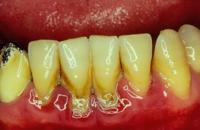

相关危害

牙石容易吸附细菌或毒素。加上牙石本身的局部刺激,可使牙龈红肿出血发炎。由于龈下牙石刺激及附着物产生的毒素,可使牙龈内侧发生溃疡,不易愈合,致使牙龈出血口臭牙周感染加重。因此,牙石是牙周炎发生、发展的重要因素。所以牙石堆积,就要去医院洁石,一般每隔半年至一年清除一次牙石为宜;牙结石附着在牙齿上,影响美观,也影响镶牙修复的效果,有了牙结石,活动假牙(又称可摘义齿)就会与牙面不密合,容易导致食物残屑积存在假牙上,引起口腔发炎。所以结石较多的人,镶牙前也要去洁牙。

沉积在龈缘龈沟内的结石,对牙龈造成持续性的刺激和压迫,使牙龈组织发生局部营养障碍,抗菌能力降低,牙龈易出现炎症、出血、萎缩,严重时可引发牙周脓肿、牙齿松动、脱落,破坏牙列完整,妨碍咀嚼功能,加重消化道负担,影响机体健康。